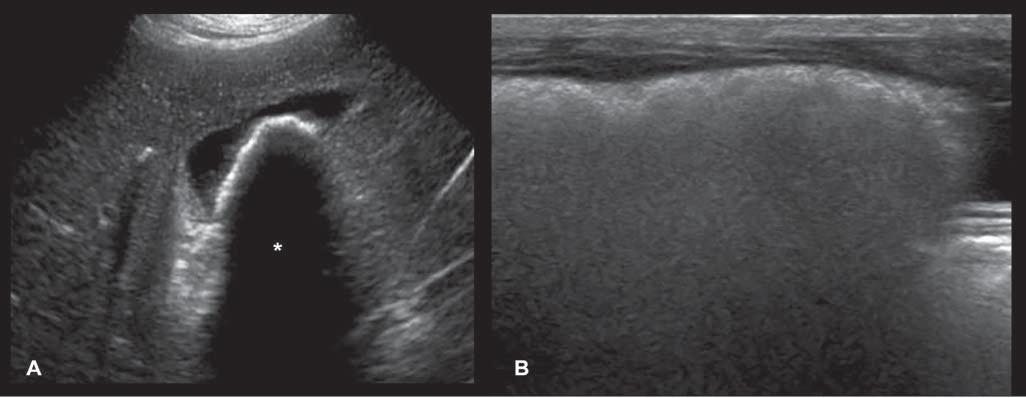

With colorDoppler,acolormapisusedtodisplay thedirectionandvelocityofthebloodflow.Thesize

andlocationoftheinterrogationboxareadjusted toprovideanoverallviewoftheflowinagiven region,andsuperimposedontheB-modeimagefor anatomicallocalization.ColorDopplerisessentialfor cardiacevaluation(seeChapter5),butcanalsoserve intheassessmentofotherbodyparts.Itallowsrapid identificationofvesselsandevaluationoftheirflow characteristics,aswellasdetectingaberrantvessels suchasportosystemicshuntsorarteriovenousfistulas andassessingtissueperfusion ColorDopplermode

PowerDoppler –alsoknownasenergyorangioDoppler–ismoresensitivetoflowsoflowvelocity asitdisplaysthesummationofalloftheDoppler shiftsignalsratherthanthemeaninagivenarea. Thismodeisfavoredforconfirmingorinformingthe presenceofbloodflow,particularlyinsmallervessels, ortodifferentiatebloodvesselsfromothertubular structuressuchasthecommonbileduct(Figure1.11).

However,asopposedtothecolormode,itdoesnot provideinformationonthedirectionorvelocityof bloodflow.Mostnewerultrasoundsystemsnowoffer ahybridcolormodecombiningthesetwomodes.